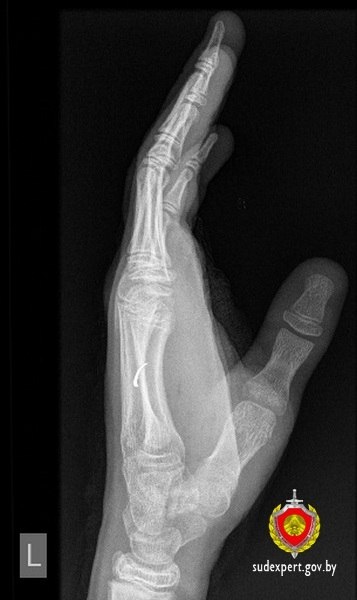

❗️В Петриковском районе 13-летний подросток прострелил руку строительным патроном

❗️В Петриковском районе 13-летний подросток

прострелил

руку строительным патроном